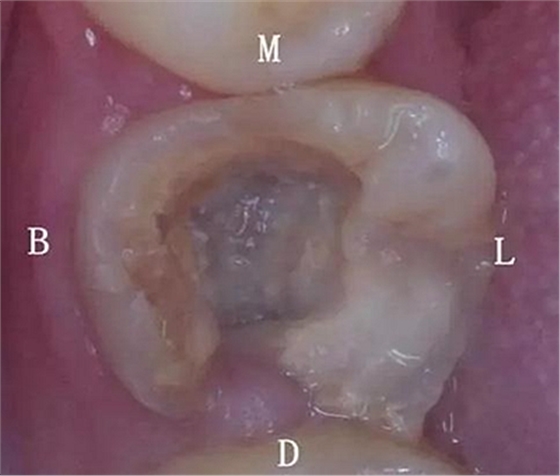

患者:男,23歲,左下六治療過,充填體脫落,慢性牙髓炎癥狀

初診時口內(nèi)照片:

初診時X光片:根分歧炎癥懷疑有底穿,和患者交待病情和費用后開始治療。